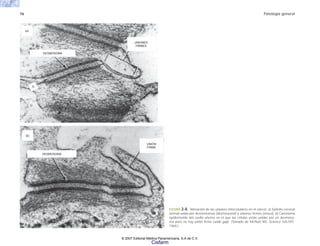

FIGURA 2-8. Alteración de las uniones intercelulares en el cáncer. a) Epitelio cervical

normal unido por desmosomas (desmosome) y uniones firmes (nexus). b) Carcinoma

epidermoide del cuello uterino en el que las células están unidas por un desmoso-

ma pero no hay unión firme (wide gap). (Tomado de McNutt NS. Science 165:597.

1969.)